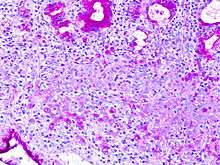

In histology, a signet ring cell is a cell with a large vacuole, the malignant type is seen predominantly in carcinomas.

The name of the cell comes from its appearance; signet ring cells resemble signet rings. They contain a large amount of mucin, which pushes the nucleus to the cell periphery. The pool of mucin in a signet ring cell mimics the appearance of a finger hole and the nucleus mimics the appearance of the face of the ring in profile.